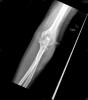

Prótesis completa de rodilla. Situación postquirúrgica.

Prótesis completa de rodilla. Situación postquirúrgica. Lateral.

Prótesis completa de rodilla.Lateral.

Prótesis completa de rodilla. Frontal.